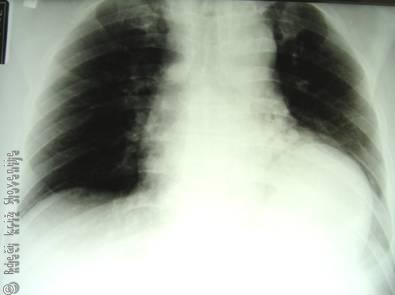

Nestabilna prsna stena

Kadar je koščeni del prsnega koša poškodovan v tolikšnem obsegu, da je porušena zgradba in funkcija prsne stene, govorimo o nestabilni prsni steni.

Pri nestabilnem prsnem košu je dihanje vedno ogroženo. Pojavi se, kadar so dvakratno ali večkratno zlomljena 3 ali več zaporednih reber, pri čemer nastane paradoksno gibanje tega dela prsne stene. Tudi zdravi, mladi poškodovanec je lahko hitro v smrtni nevarnosti, kar toliko bolj velja za starejše. Takšna poškodba nastane pri neposrednem delovanju velike sile na prsno steno.

Slika 7

A – Nestabilni prsni koš zaradi dvojnih zlomov več reber.

B – Pri izdihu se poškodovani del prsne stene izboči, pri vdihu pa vdre.

Stanje diagnosticiramo na pogled. Ni težko ugotoviti paradoksnega gibanja prizadetega dela prsne stene, ki se pri vdihu vdre, pri izdihu pa izboči. Takšno gibanje stene ima za posledico neučinkovito predihavanje pljuč in povečano dihalno delo.